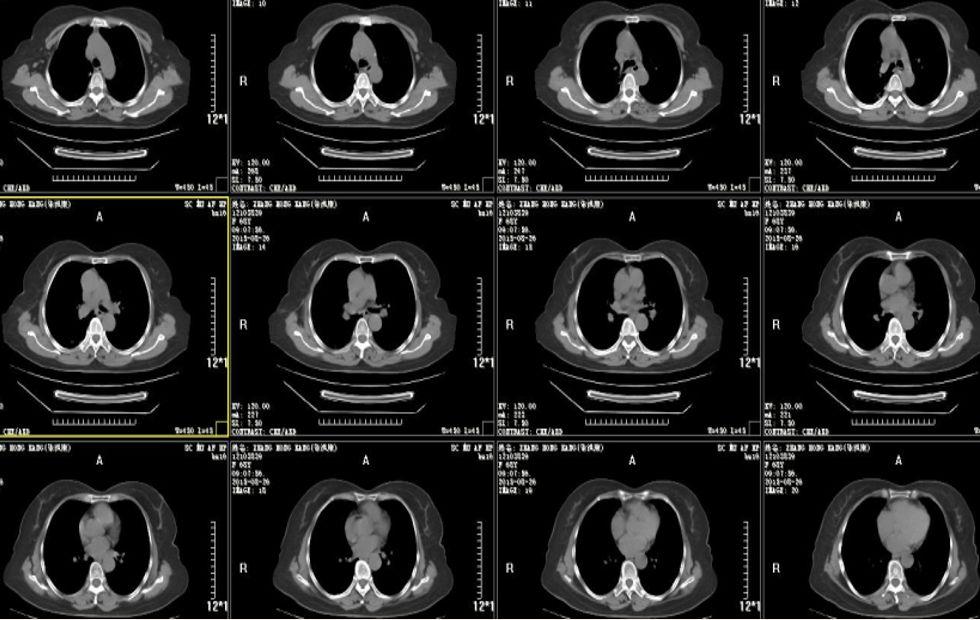

晚期不可切除非小细胞肺癌病例分享一例腺癌

图片尺寸1440x1080